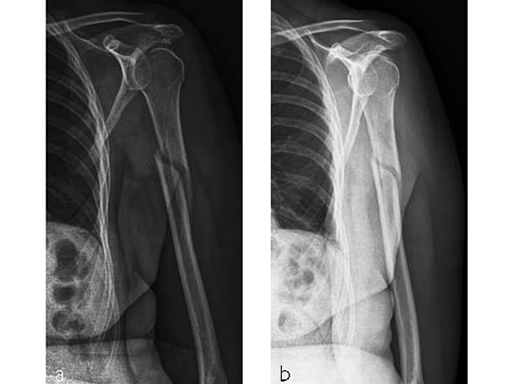

Case 1: A three-part valgus impacted fracture of the proximal humerus in a 47-year-old woman.

Case 2: Three-part valgus displaced fracture of the proximal humerus in a 63-year-old man.

The tuberosities have been reduced and fixed using intertubercular sutures (Fig 4). To reconstruct the medial support a calcar screw has been used. This determines the height of the nail. Therefore a 1 cm end cap has been used to get support for the proximal end of the nail in the part of the bone with the best bone quality.